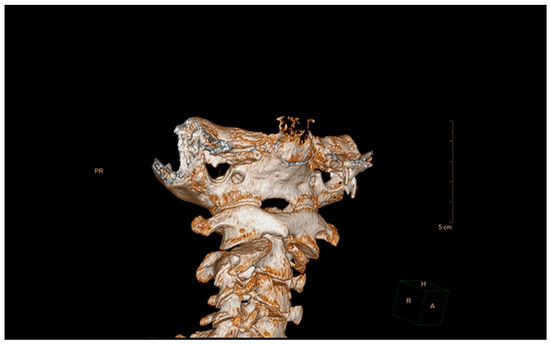

5.2. Computed Tomography (CT)

5.3. Magnetic Resonance Imaging (MRI)